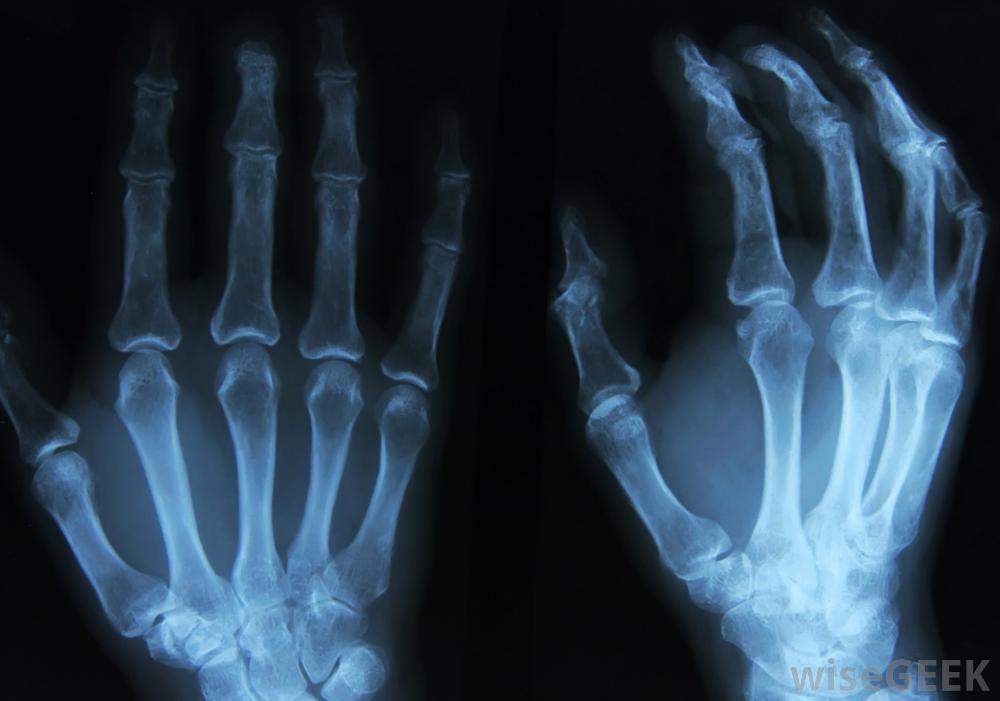

a罗兰多骨折通常是用X光片来诊断的。拇指骨折会使人非常虚弱。班纳特骨折是另一种发生在拇指根部的骨折,但这种骨折通常没有罗兰多严重骨折。在Rolando骨折中,拇指根部的骨头通常至少分成三块。很多时候,骨折会是Y形或T形

如果不能固定骨折的拇指,可能会导致骨骼的不正常愈合。当拇指或手碰到非常坚硬的表面时,可能会发生Rolando骨折。这可能发生在人拳打脚踢时坚硬的东西,例如墙。它也可能发生在摔倒时。剧烈疼痛是罗兰多骨折最常见的症状。手通常会非常柔软,尤其是拇指根部。患有这种病的人拇指骨折的类型通常不能很好地移动他的拇指。肿胀和瘀伤也可能发生。医学专家建议有这些症状的患者尽快就医。可能导致治疗延迟在有限的手部使用中。Rolando骨折通常通过x光片诊断。Rolando骨折的治疗通常需要手术。在许多情况下,重建拇指关节可能需要金属螺钉和销钉,克氏针,也可以用来压缩骨头碎片直到愈合。严重的Rolando骨折患者即使在骨折愈合后也会感到疼痛或拇指使用受限。通常,骨头碎裂得越多,预后就越差如果在治疗过程中骨骼排列不正确,也可能导致拇指功能受限。